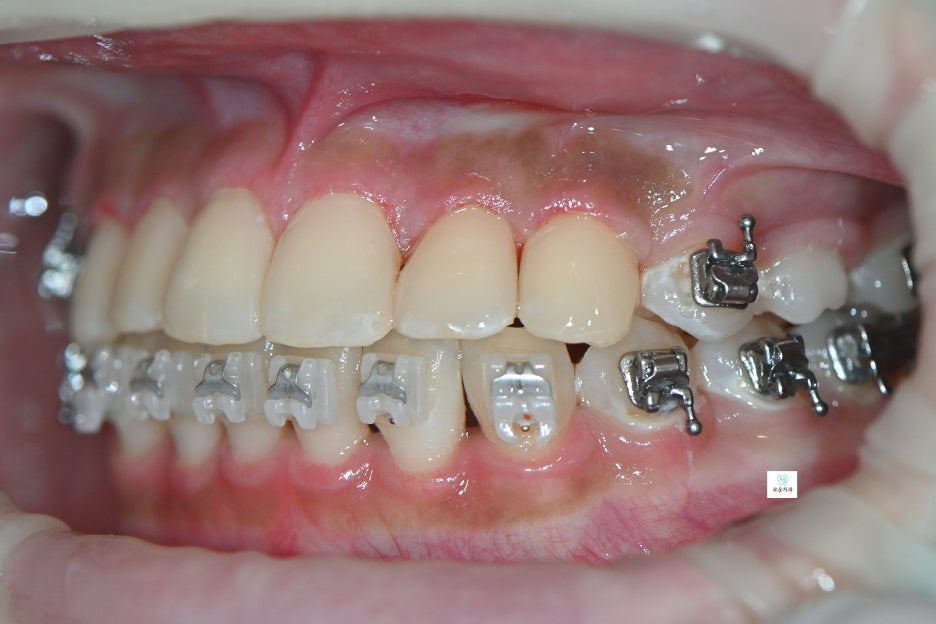

“교정 중 브라켓 주변 충치 치료 사례”

브라켓 주변에 여러 개의 충치가 발생하여

장치를 제거한 후 치료를 진행한 사례입니다.

한 치아 기준 약 3면 정도의 우식이 확인되어

충치 제거 후 수복 치료를 진행했습니다.

앞니 치료를 먼저 시행한 후

소구치와 대구치 부위 충치까지

순차적으로 치료를 완료했습니다.

자연스럽고 깔끔하게 마무리된

앞니 치료 결과를 확인할 수 있습니다.